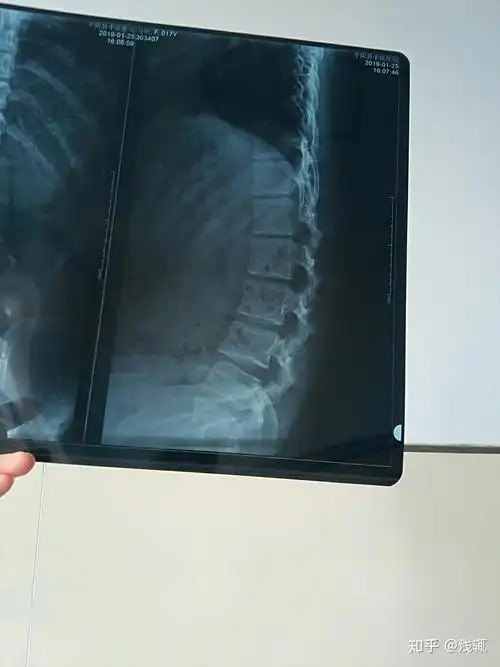

先天腰间盘突出,脊柱达到45度弯曲的人有多痛苦?